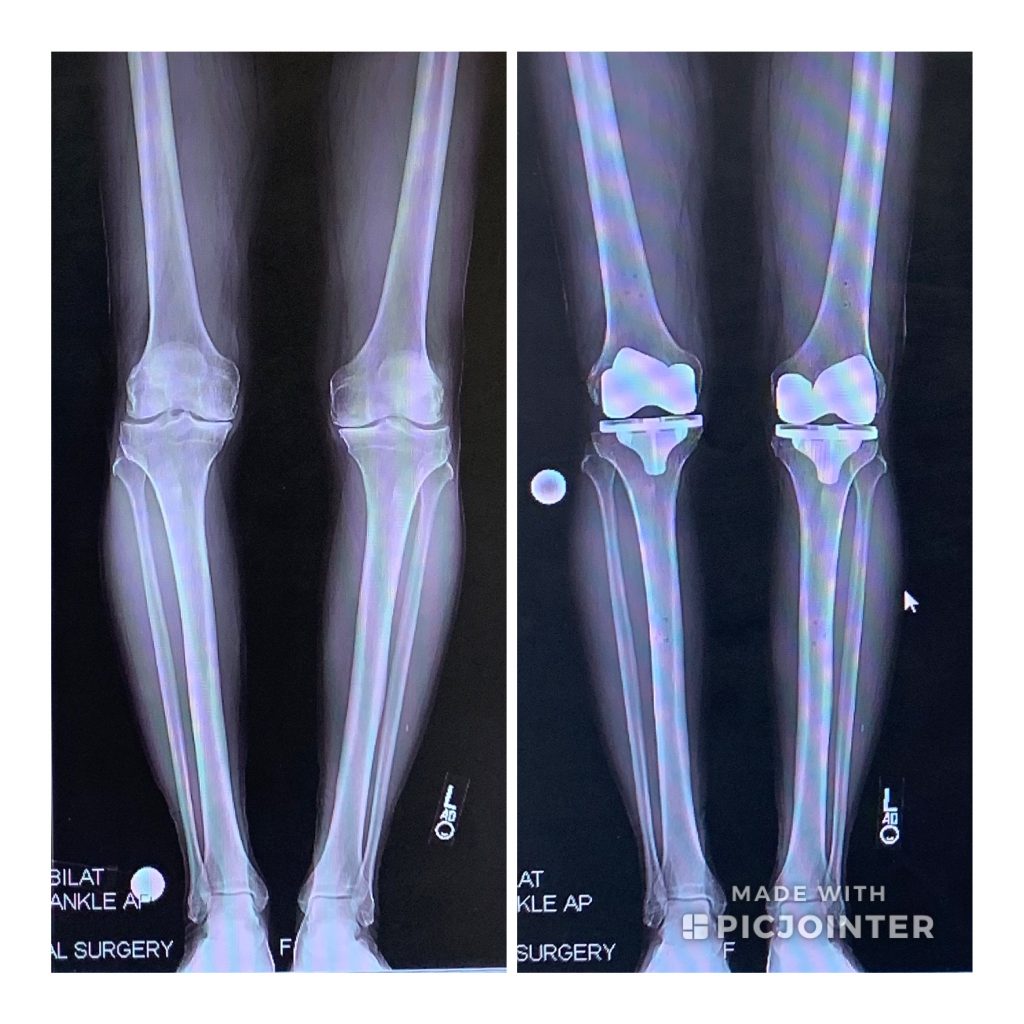

What a great experience!!! I was knock kneed and "pigeon toed" all of my life, which made it difficult to enjoy or compete in gymnastics. I later took to studying dance in high school and was below average as the 1st position in dance requires to touch your heels. The better "straight leg" you were, the better you performed in dance. At this point in my life, I do participate in liturgical dance in the Christian church that I attend and the movements were still challenging as it incorporates all of the same principles that I learned in dance from John Dewey High School. Over the years I developed Osteoarthritis in both knees, which affected my daily life activities. After the knee replacement surgery, now I just feel wonderful and I am grateful for the decision to have bilateral knee replacement surgery at HSS on Tuesday, 2/21/17. As I am writing this, I have not taken pain medications since I was released from a local acute rehab facility. The occupational and physical therapists were great there as well. Today is Friday, 3/10/17, and I live alone and I am managing the staircases in my 3-level single home. The best result is no more pain in the knees. I look forward to Summer 2017 as I feel wonderful. All the best to Dr. Peter Sculco and the tremendous HSS staff. The nurse care was quite exceptional and responded to my bell calls with a smile and compassion.